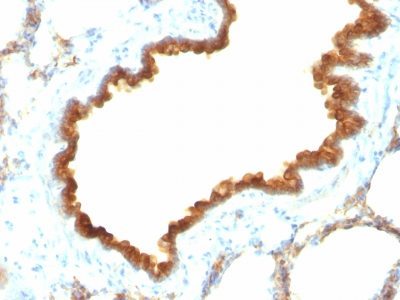

Recognizes a protein of 40 kDa, identified as cytokeratin-19 (CK19), which is expressed in sweat gland, mammary gland ductal and secretory cells, bile ducts, gastrointestinal tract, bladder urothelium, oral epithelia, esophagus, and ectocervical epithelium. Anti-CK19 reacts with a wide variety of epithelial malignancies including adenocarcinomas of the colon, stomach, pancreas, biliary tract, liver, and breast. Perhaps the most useful application is the identification of thyroid carcinoma of the papillary type, although 50%-60% of follicular carcinomas are also labeled. Anti-CK19 is a useful marker for detection of tumor cells in lymph nodes, peripheral blood, bone marrow and breast cancer.